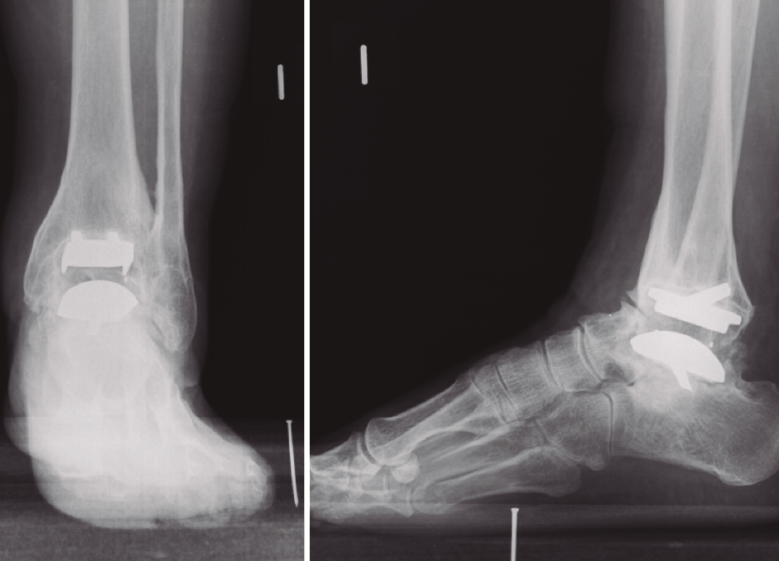

En el tratamiento de las artropatías graves del tobillo, la prótesis total es un procedimiento que está alcanzando niveles de eficacia y seguridad cada vez mayores. En muchos casos de fracaso por aflojamiento aséptico, no es posible el recambio de componentes y precisamos realizar una artrodesis como procedimiento de salvamento.

El tantalio, por sus características de biocompatibilidad y resistencia, se ha utilizado para la reconstrucción de grandes defectos óseos en articulaciones como la cadera.

La utilización de espaciadores de tantalio en el tobillo asociados a un clavo tibiotalocalcáneo permite la artrodesis sin perder longitud del espacio articular, evitando la dismetría de miembros.

Hemos estudiado 4 casos de artrodesis tibiotalocalcánea con espaciador de calcáneo por fracaso aséptico de prótesis de tobillo. El tiempo de seguimiento medio ha sido de 26 meses en 3 de los casos recogidos (20-37 meses), aunque el tiempo de seguimiento en el caso intervenido más recientemente es de 7 meses. Los resultados fueron valorados utilizando las escalas de valoración visual analógica (EVA) y de la American Orthopaedic Foot and Ankle Society (AOFAS).

Todos los casos han presentado buenos resultados clínicos e integración radiológica del implante. No se han producido complicaciones relacionadas con el material y los pacientes han mostrado satisfacción con el procedimiento. Creemos que los espaciadores de tantalio son una opción útil y segura en la artrodesis por fracaso aséptico de prótesis de tobillo.